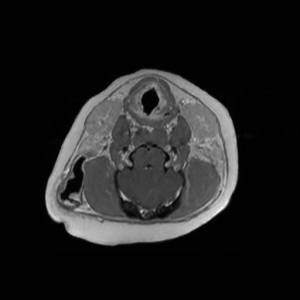

Main Gallery

Playing with a photo gallery function. It is possible to have multiple galleries, each within a namespace.